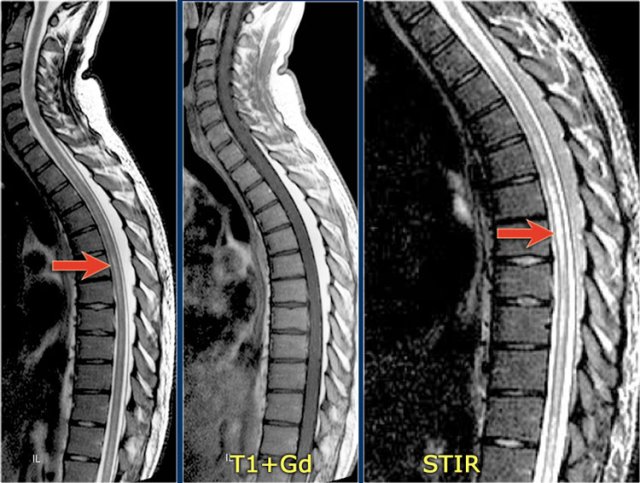

The sagittal image shows a large segment of hyperintensity on T2WI.

The transverse image shows that most of the cord is involved.

These images are of a 31 year old male with headache, voiding disturbances, urinary retention, sensory level C3.

The CSF analysis revealed 400/3 cells (meaning no infection) and a slightly higher protein level.

The images show a long segment myelopathy with full transverse involvement.

There is no swelling and no enhancement.

It does not look like MS or tumor, so we are thinking ATM - acute transverse myelitis.

Here images of a typical case of TM.

There is multisegment high signal on STIR and T2WI with some swelling.

Most of the cord in the transverse diameter is involved.

There is no enhancement, which is usually the case in TM.

Sometimes there is some patchy enhancement.